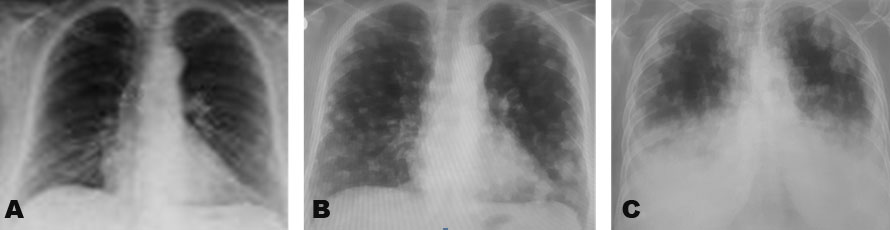

CT imaging confirmed widespread local and distant metastases in bladder, liver, and lung (Figure 3). Diffused distribution in multiple nodules were observed using posteroanterior and lateral chest teleradiography. Diffused pulmonary nodules suggested metastatic infiltration (Figure 4). The patient was weak and lost the ability to breathe, requiring a supply of oxygen. The patient also needed a urinary catheter and suffered from frequent constipation. In less than a month after performing the CT, she died (March 18, 2020), two days before the start of her chemotherapy regimen.

Figure 4: Diffused distribution in multiple nodules was observed progressively using posteroanterior and lateral chest teleradiography, suggesting metastatic infiltration. (A) November 28, 2019 (before hysterectomy), (B) February 21, 2020, and (C) March 12, 2020.